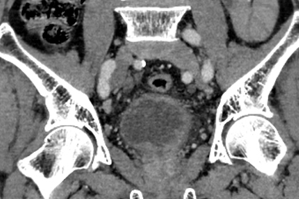

多年来,贵州航天医院各科室紧跟医学前沿,不断强技术、补短板,大力开展新技术、新项目,完成了许多高精尖、高难度、本地区“首例”的技术,填补了医院医疗技术空白,满足了群众日益增长的医疗需求。 本期,我们将为大家带来泌尿外科特色技术——腹腔镜膀胱癌根治术+原位新膀胱术,保留患者自然排尿功能。 案例分享 患者(60岁)在当地医院检查发现膀胱多发肿瘤,在行膀胱肿瘤电切术后,病理提示:高级别尿路上皮癌,该院医生建议患者进行根治性膀胱切除,但切除后肚子上将存在永久造瘘并需佩戴腹壁尿袋,尿液不能自己控制,随时会从肚子流出。 患者拒绝接受挂尿袋的方式,在辗转多个医院咨询后,得知贵州航天医院泌尿外科具有切除膀胱后肚子上不用佩戴尿袋的技术,于是前来我院就诊。泌尿外科腔镜组组长李凯教授带领团队经过反复研究病史及阅片,充分考虑患者需求并征得患者及家属同意后,决定为患者实施腹腔镜根治性膀胱切除术+原位回肠新膀胱术。 CT示膀胱内多发肿瘤 经过6个多小时紧张的手术,顺利切除膀胱并取长约40cm的肠管重新整合成新膀胱,再与输尿管、尿道吻合后原位代替病变的膀胱。切除的组织经过病理检测,提示:恶性上皮肿瘤,符合膀胱高级别浸润性尿路上皮癌,侵及深肌层。 术后3天,患者可以正常排尿;1周后顺利出院;1月后拔出双侧单J管及尿管,患者反馈小便顺畅,无尿失禁等不良情况出现;3月后患者进行尿流率检测,自主排尿通畅。 术后腹壁伤口愈合良好 患者术后3月新膀胱影像 术后3月,患者行尿流率检测 自主排尿通畅 腹腔镜膀胱癌根治术+原位新膀胱术代表了现代泌尿外科技术的最高水平,它不仅为膀胱癌患者提供了根治肿瘤的机会,还通过微创技术和功能重建,帮助患者重获高质量的生活。贵州航天医院泌尿外科李凯教授团队结合患者实际情况对该技术进行了改良,全手工缝合新膀胱,确保患者排尿正常且避免了结石等并发症的出现,已完成多例手术,在遵义地区处于一流水平,为遵义地区患者健康保驾护航。 咨询信息:贵州航天医院便民服务电话 什么是腹腔镜膀胱癌根治术+ 原位新膀胱术 膀胱癌是泌尿系统常见的恶性肿瘤之一,传统的手术方式虽然有效,但创伤大、恢复慢,患者需终生佩戴腹壁尿袋,生活不便且影响社交,给患者带来了极大的身体和心理负担。随着医学技术的不断进步,腹腔镜膀胱癌根治术+原位新膀胱术成为治疗膀胱癌的先进选择,以其精准、微创、恢复快的优势,为患者带来了新的选择和希望。 腹腔镜膀胱癌根治术+原位 新膀胱术原理 腹腔镜膀胱癌根治术是一种微创手术,通过腹腔镜技术,医生可以在高清影像的引导下,精准切除病变的膀胱及周围可能受侵的组织。与传统开腹手术相比,腹腔镜手术切口小、出血少、术后疼痛轻,患者恢复更快。 原位新膀胱术则是在切除膀胱后,利用患者自身的肠道组织(通常为回肠)构建一个新的膀胱,并将其与尿道连接,使患者能够通过正常途径排尿,极大提高了术后生活质量。相比传统的尿流改道术(如回肠代膀胱术),原位新膀胱术更符合生理结构,患者无需佩戴尿袋,生活质量显著提升。 腹腔镜膀胱癌根治术+原位 新膀胱术优势 (一)微创精准,减少创伤 腹腔镜手术通过几个小切口完成操作,避免了传统开腹手术的大切口,减少了术中出血和组织损伤,术后疼痛轻,恢复快。 (二)原位新膀胱,恢复自然排尿功能 原位新膀胱术重建了患者的排尿功能,术后患者可以通过尿道正常排尿,避免了佩戴尿袋的不便和心理压力。 (三)术后并发症少,恢复快 由于手术创伤小,术后感染、肠梗阻等并发症的发生率显著降低,患者住院时间短,能够更快回归正常生活。 (四)提高生活质量 原位新膀胱术不仅保留了患者的排尿功能,还减少了术后对生活的影响,患者可以更好地融入社会和工作。 术后康复与护理 术后患者需遵循医生的指导,逐步恢复饮食和活动。早期可能需要进行膀胱功能训练,以适应新膀胱的排尿功能,定期复查和随访是确保术后长期效果的关键。 友情提醒: 发现无痛性肉眼血尿,需警惕泌尿系肿瘤,尤其是发病率较高的膀胱癌,须尽早就诊。 贵州航天医院泌尿外科专家团队 石 英 泌尿外科主 任 学科带头人 主任医师 中国医师协会泌尿外科分会感染协作组委员,奥林巴斯泌尿系软镜西南区专家组成员,西南地区第一批输尿管软镜专家组成员,贵州省医学会泌尿外科分会委员,贵州省性学会理事,贵州省性学会常务委员,贵州省泌尿外科专业医疗质量控制中心专家委员会委员。 从事泌尿外科专业近30年,熟练掌握泌尿系各类疾病的诊治,具有丰富的临床经验,擅长泌尿系结石、腹膜后肿瘤及泌尿系肿瘤的手术治疗,对泌尿系感染、泌尿系结核、尿源性脓毒血症的救治有独到的见解及抢救经验,在贵州省率先引入输尿管软镜技术,同时在男科领域,对男性阳痿、早泄及前列腺疾病有很深的研究。 李 凯 泌 尿 外 科 副 主 任 医 师 贵州航天医院肿瘤腔镜组带头人,擅长肾癌根治术、输尿管癌根治术、膀胱及前列腺癌根治术、腹腔镜输尿管狭窄切除吻合术、输尿管切开取石术等手术,在遵义市率先开展泌尿系结核后膀胱挛缩全腹腔镜下膀胱扩大术。 贵州省医学会泌尿外科分会青年委员,遵义市医学会男科分会常务委员,遵义市医学会泌尿外科分会常务委员。 李国成 泌 尿 外 科 副 主 任 医 师 中国人体健康科技促进会男科学专业委员会委员,贵州省性学会泌尿外科分会委员,贵州省医学会男科学分会委员,遵义市医学会男科学分会副主任委员兼秘书长,遵义市医学会泌尿外科分会常务委员,贵州航天医院男科带头人。 从事泌尿外科及男科工作10余年,曾多次在上海交通大学附属第一人民医院,中国中医科学院西苑医院进修学习男科;擅长性功能障碍的诊治,男性整形手术,前列腺增生激光手术,显微手术等。 贵州航天医院泌尿外科简介 • ✦ 基本情况 ✦ • 贵州航天医院泌尿外科创建于1968年,经过几代人的努力,微创与内镜手术占比达90%以上。是贵州省临床重点专科建设单位、北京清华长庚医院李建新教授团队诊疗及会诊中心、北京医学会尿路修复与重建诊疗及会诊中心、上海公济泌尿外科集团遵义中心、上海援黔专家李铮教授男科工作室、贵州省泌尿外科质量控制专家委员单位,科室亚专业框架已完善。 • ✦ 专科特色技术 ✦ • (一)泌尿系结石内镜碎石技术 泌尿系结石微创治疗领域方面是贵州省首家引进科医人钬激光碎石技术科室,在遵义地区率先掌握输尿管硬镜、软性镜,经皮肾镜钬激光碎石技术。目前是北京清华长庚医院泌尿外科“手把手”经皮肾镜碎石技术培训基地、贵州省输尿管软镜培训基地。 1.负压吸引可弯曲软镜鞘电子软镜碎石术 2.标准与超微通道相结合的经皮肾镜碎石取石术 (二)微创腹腔镜技术 泌尿外科腹腔镜技术师承于浙江省人民医院、北大、北京解放军总医院。目前采用经腹、经后腹双入路法的腹腔镜技术完成肾部分切除、肾切除、肾输尿管全长切除、肾盂输尿管成形、输尿管狭窄吻合、膀胱翻瓣等手术。在遵义地区率先掌握腹腔镜下膀胱癌根治术、腹腔镜下前列腺癌根治术。 (三)男科、盆底技术临床应用 遵义地区男科分会主委单位,是贵州省首家引进尿动力学检查并取得了全国资质认证科室,也是贵州省首家进行RigiScan检查的单位。在遵义地区率先掌握显微取精子技术以及显微镜下治疗精索静脉曲张、显微镜下输精管吻合、输精管附睾吻合技术。率先采用前列腺激光剜除术治疗前列腺增生症。在陆军军医大学西南医院泌尿外科主任沈文浩教授指导下,完成遵义市首例神经源性膀胱骶神经调节刺激器置入术。 • ✦ 诊疗范围 ✦ • 诊疗范围(除外肾移植、癌栓):泌尿系结石、泌尿系肿瘤、肾上腺疾病、肾积水、前列腺增生、男性生殖器功能障碍(精索静脉曲张、生殖道感染、输精管梗阻等)、盆底功能障碍性疾病(膀胱脱垂、排尿功能异常、尿失禁)、泌尿生殖系畸形。 泌尿外科拥有独立门诊治疗室、日间手术室、尿动力学检查室、精液分析检查室、男性勃起功能检查及治疗室、ESWL治疗室、结石分析检查室。